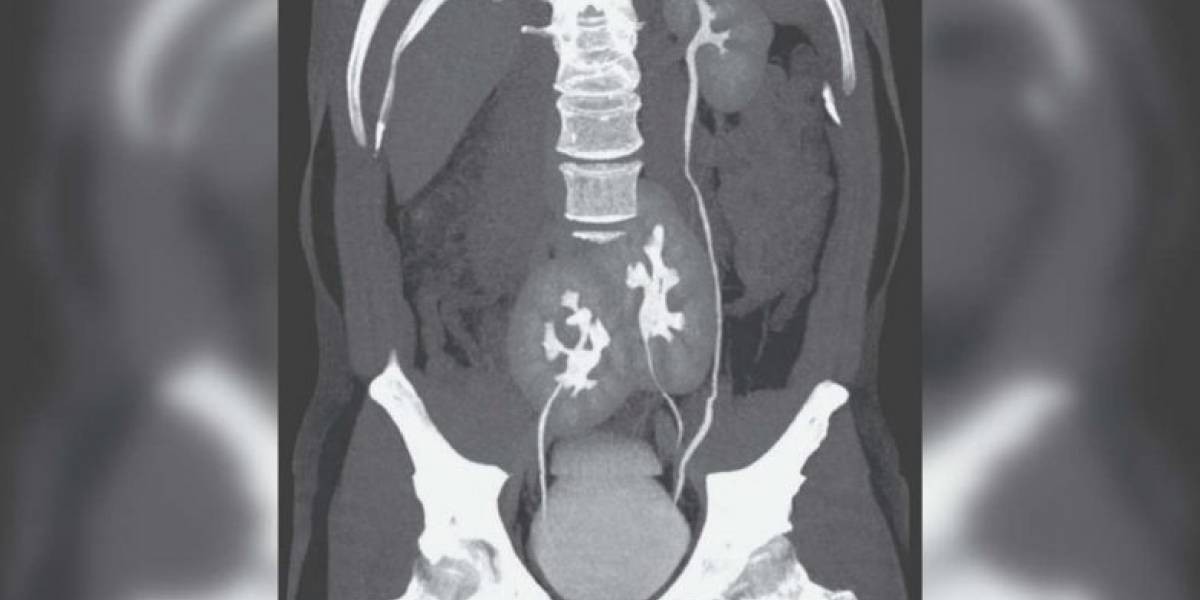

Las sospechas del equipo médico cuando el hombre contó los síntomas, apuntaban a una hernia discal, en la columna vertebral. Los médicos le pidieron una Tomografía Axial Computarizada (TAC), e hicieron el hallazgo.

Los médicos determinaron que la función renal del hombre es totalmente normal. "Tiene un riñón normal en el lado izquierdo y otro atrofiado y doble en el lado derecho", agregó el informe de la revista especializada.